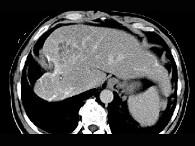

问题 女性,56岁,腹胀、双下肢水肿、乏力、食欲不振,影像所见如下图,最佳的诊断是 ( )

选项 A.酒精性肝硬化并肝血管瘤 B.血吸虫肝硬化并肝癌 C.肝炎后肝硬化并肝癌 D.局限性脂肪肝 E.原发性肝癌

答案 B